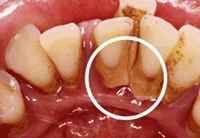

歯石の除去

歯の周りに磨き残しが多いと、唾液の中のカルシウムの成分と一緒になって、歯石が付着します。

歯石があると、さらに磨き残しができやすいですし、歯石自体に何千、何億もの細菌が住み着いてしまいます。その結果、歯ぐきが腫れたり、歯周病の原因となります。歯周病を予防するため、定期的に歯石を除去しましょう!